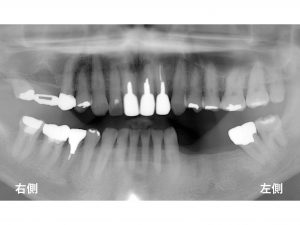

以下が初診時です。

下顎左側の奥歯が欠損しているのでインプラント治療をご希望されて来院されました。

左下奥歯が3歯欠損しています。

2本のインプラントでブリッジを計画しました。

以下のように上顎前歯部が欠損していました。

他の歯科医院で前歯を抜歯されたそうです。

抜歯後に義歯(入れ歯)を作成したそうですが、

義歯に非常に強い違和感があり、

使えないとのことで

再度当院を受診されました。

欠損部の左側の歯に問題がありました。

歯自体は、動揺しており、

亀裂も認められました。

基本的にこの歯は抜歯が必要な状態でした。